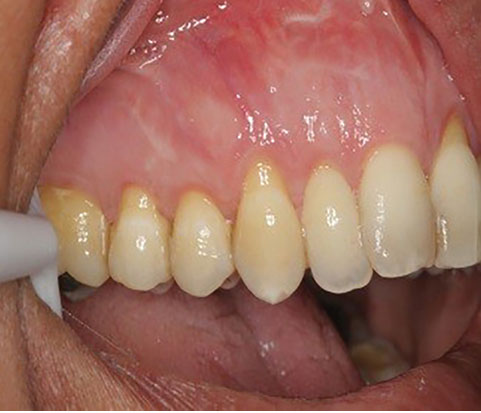

The sulcular incision was made at the recipient site. The flap was beveled in the interdental papilla region adjacent to the tooth with the exposed root. A partial-thickness flap was raised beyond the mucogingival junction. The mesiodistal width of the incision was extended to the line angle of the adjacent teeth mesially and distally. Mesial and distal vertical releasing incisions were also made. The required graft width was measured using a periodontal probe. A connective tissue graft was prepared from the palate, measuring 1–1.5 mm in thickness and fixed at the recipient site with a 4-0 bio-absorbable polyglycolic suture. Then, a coronally repositioned flap was relocated to cover the graft and stabilized in the site with a sling suture (Figures 1 and 2). A 10×20-mm and 0.6–0.9-mm-thick graft was prepared from acellular dermal matrix graft [Cenoderm, Tissue Regeneration Corporation (TRC), Iran] (Figure 3) according to the manufacturer’s instructions. The graft was placed at the recipient site from its porous surface from the CEJ to 2–3 mm beyond the bony margin of dehiscence and fixed at the recipient site with a 4-0 bio-absorbable polyglycolic suture. Then, a coronally repositioned flap was relocated to cover the graft and stabilized with a sling suture (Figures 4 and 5).

Figure 1.

SCTG site before surgery.